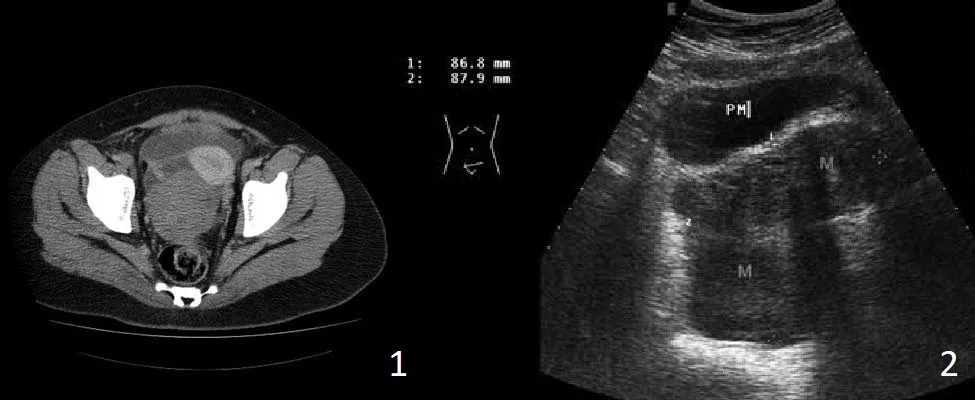

Obraz radiologiczny TK przedstawiający objaw masy.

Ryc. F: 1 – obraz TK, gdzie masy nowotworowe rozwijające się w miednicy przemiszczają za pomocą efektu masy macicę i pęcherz moczowy. 2 – USG, które uwidacznia zajęcie jajników.